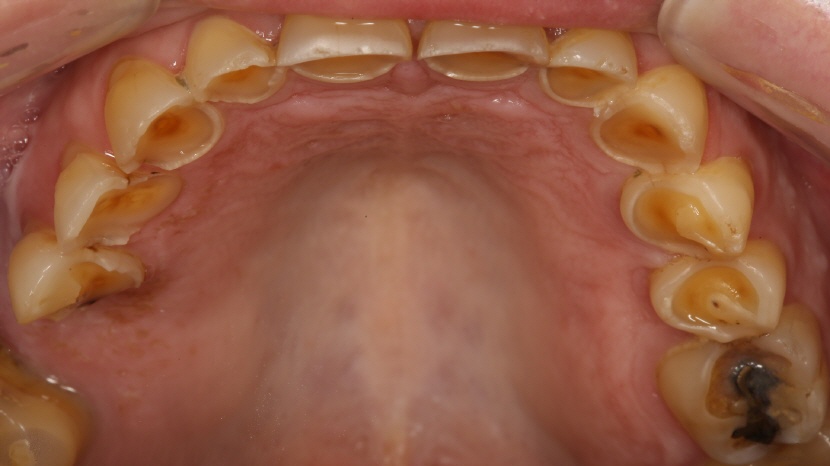

• Aufbissansicht des Oberkiefers

Deutlich sichtbarer, generalisierter Schmelz- und Dentinverlust.

• Aufbissansicht nacht der Therapie

Die Brücke im Oberkiefer links, wie auch die Brücke im Unterkiefer rechts, wurden durch den Zahntechniker (N. Lanfranconi, Zürich) volldigital aus Zirkon hergestellt